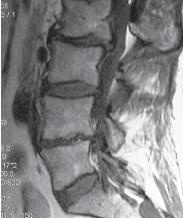

На МРТ №°103 наблюдается грыжа межпозвонкового диска в сегменте LIV-LV, частично компенсированная спондилёзом, гипертрофия задней продольной связки и выраженный эпидурит на данном уровне. В сегменте LV-SI наблюдается протрузия межпозвонкового диска, компенсированная спондилёзом. На уровне этих же сегментов наблюдается рубцовоспаечный процесс, как следствие перенесённой хирургической операции — ламинэктомии, проведённой в сегментах (LIV-LV, LV-SI), с целью устранения грыжи межпозвонковых дисков и декомпрессии спинномозговых корешков на данных уровнях. Приведённый ниже случай является показательным примером, как пациентка попала к недобросовестному хирургу, который сделал ей абсолютно необоснованную операцию. ![]() На МРТ № 104 наблюдается начальная стадия дегенеративного процесса в шейном отделе позвоночника, протрузия межпозвонкового диска в сегменте CVI—CVII. На МРТ № 105 наблюдается состояние после проведённой тотальной дискэктомии с передним межтеловым спондилодезом в сегменте CV—CVII, выпрямление физиологического лордоза, абсолютный стеноз спинномозгового канала с блоком ликворных путей, секвестрированные грыжи (с краниальной миграцией секвестров) в сегментах CIV-CV, CV-CVI, CVII-ThI. Состояние пациентки после операции ухудшилось, а в течение последующего года — значительно усугубилось. В данном конкретном случае не совсем понятно, зачем сделали эту операцию? Дооперационные жалобы больной были больше сосудистого характера. Прямых показаний к операции просто не было! Если бы данная пациентка прошла медикаментозное лечение у невропатолога, без хирургического вмешательства, то сейчас её здоровье было бы намного лучше, да и будущее бы не вызывало опасений в плане последующих осложнений. Вот ещё трагический случай во время проведения необоснованной операции. ![]() На МРТ № 106 состояние шейного отдела пациентки до операции. Наблюдается сглаженность физиологического лордоза, ликворные пути свободны, компенсированные протрузии межпозвонковых дисков в сегментах СIII—СIV На МРТ № 107 состояние шейного отдела той же пациентки после дискэктомии с межтеловым спондилодезом в сегменте CV—CVI, кроме того наблюдается травма спинного мозга на данном уровне хирургической фрезой. Если до операции у данной пациентки были незначительные вертебробазилярные нарушения, то после… Травма спинного мозга хирургической фрезой — это, конечно, трагическая случайность. Ведь от ошибок никто не застрахован и добросовестный врач никогда не даст гарантии на положительный исход любого вида лечения. Но в данном случае проведение самой операции было абсолютно необоснованным, фактически она превратила нормального человека в инвалида. Следующий пример также демонстрирует, какие бывают последствия после дискэктомии с межтеловым спондилодезом. |